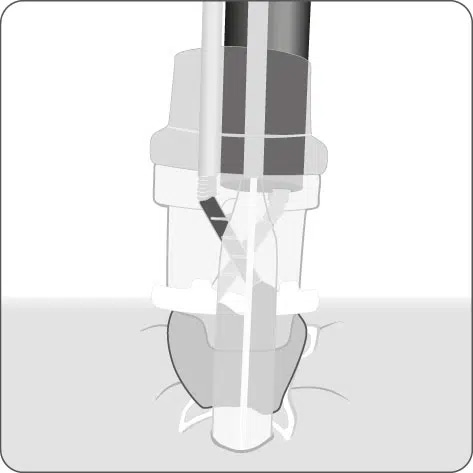

Positionsermittlung

Die korrekte Positionierung der BARS® Anchor ist entscheidend für eine erfolgreiche Behandlung.

- Mit einer gedachten Mittellinie die Anastomose in zwei Hälften teilen.

X = Austrittspunkt Endoskoparbeitskanal - Die Anchor knapp unterhalb der Mittellinie platzieren.

• = BARS® Anchor Black, • = BARS® Anchor Silver. - Der Kalibrierballon (•) definiert das Restlumen im gegenüberliegenden Halbkreis.

Anvisieren der Applikationsstelle.

Einführen des Führungsdrahts in den äußeren BARS® Arbeitskanal und Vorlegen in der Anastomose.

Einführen der Anker in den Endoskop-Arbeitskanal und den inneren BARS® Arbeitskanal.

Überkreuztes Platzieren der Anker im vorbereiteten Zielgewebe.

Platzieren des Kalibrierballons in der Anastomose. Schrittweises Einziehen des Gewebes in die BARS® Applikationskappe, mit abwechselnden Zugbewegungen.

Sicherstellen, dass das Gewebe symmetrisch in der Kappe positioniert ist. Platzieren des BARS® Clips durch Drehen des Handrads.

Zurückziehen der Instrumente und Inspektion der Clip-Applikationsstelle.